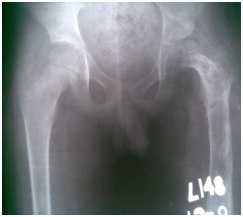

Figure 1 Initial radio graph- Femoral head dislocated supra-laterally, Shaper cook deformity of left femoral cortices are sclerosed, a large hyper dense area in the medullary cavity sequestrum. Pelvis tilted on the right.

Figure 8&9 Compare initial Radiograph and after completion of treatment.